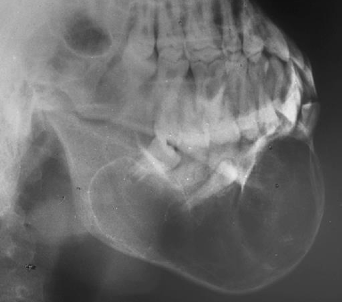

What’s an aneurysmal bone cyst?

Age: Adolescents and young adults under 30

Frequency: Rare

Site: Commonly body / posterior mandible

Size: Can become very large

Shape: Unilocular / Multilocular – may be soap bubble appearance

Outline: Smooth and well defined

Radiodensity: Radiolucent with faint random trabeculation

Effects: Teeth displaced uncommonly resorbed Ballooning expansion Rare cortical perforation